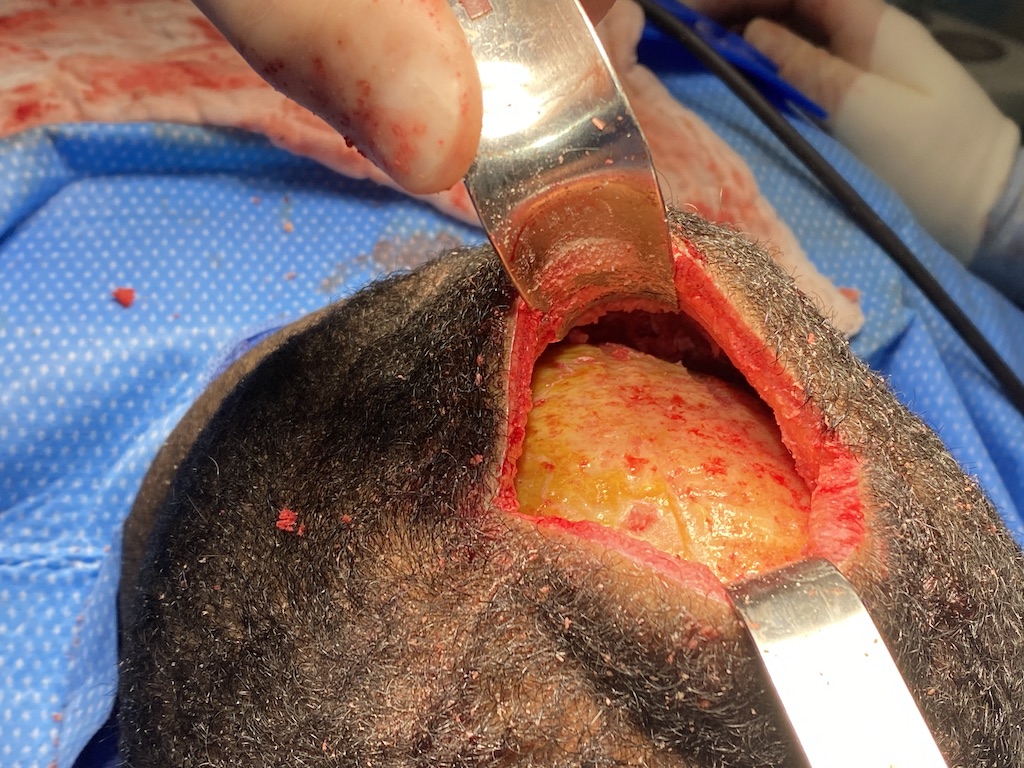

Desire for back of head skull augmentation.

Placement of custom back of head skull implant. (immediate intraop result)

Desire for back of head skull augmentation.

Placement of custom back of head skull implant. (immediate intraop result)